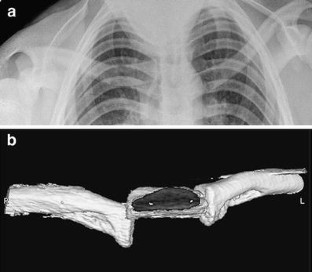

Fig. 1